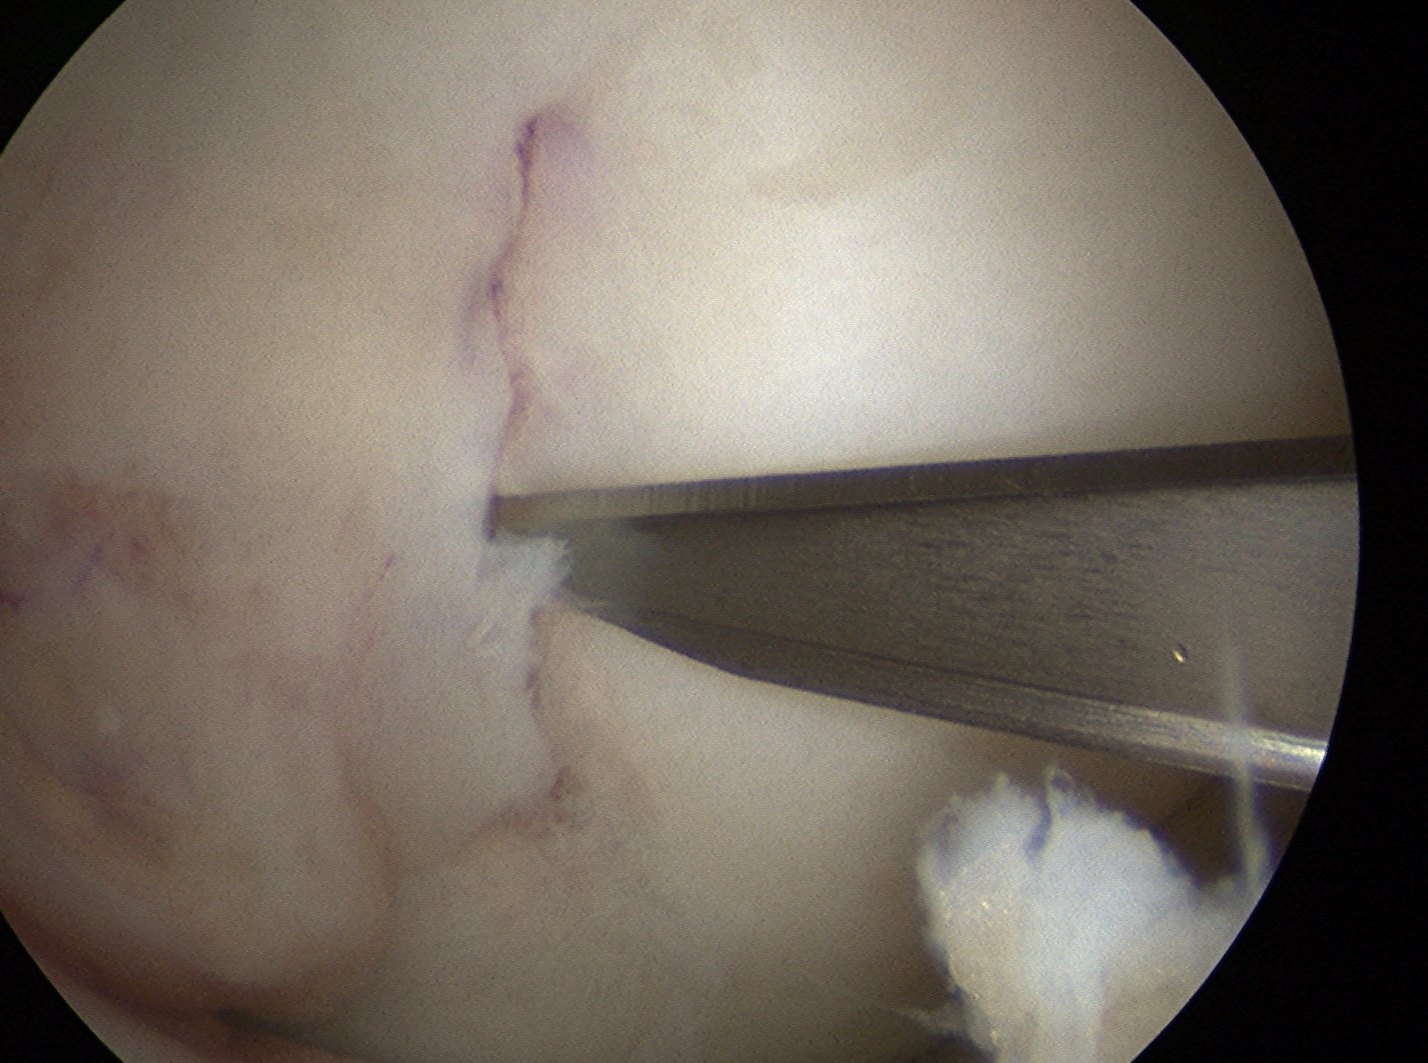

Mobilisation of fragment

Lesion carefully mobilised with scaple and probe

- left to lever open inferiorly

- want it to stay partially attached

- need to release some fibres of PCL medially

- insert spinal needle from medial knee to hold fragment open